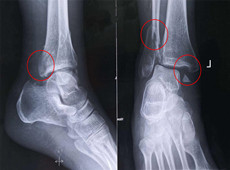

【医疗科普】踝关节骨折的主要类型及其影像学表现

大家好,我是南京医科大学第二附属医院骨科副主任医师王伯尧,从事骨科临床工作十余年,拥有丰富的骨科临床经验,主要研究方向为骨科手术机器人的开发与临床应用,今天跟大家介绍踝关节骨折的几种常见类型及其在X影像上的表现。接下来跟...